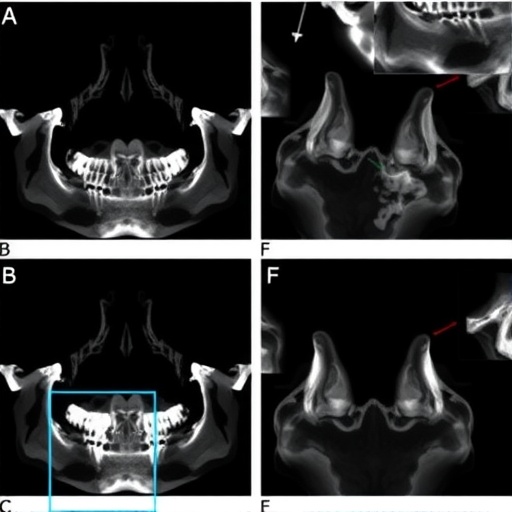

In this comprehensive study, Ono and colleagues embarked on a dual-pronged approach. First, they conducted a genetic association analysis in a well-defined patient cohort diagnosed with TMJ OA, examining the prevalence of SNPs within two candidate gene loci, FILIP1-SENP6 and FTO. Concurrently, they employed advanced in silico computational modeling to predict the functional impacts of these polymorphisms on gene expression and protein interactions relevant to cartilage homeostasis and inflammatory response modulation.

The in silico component of the investigation utilized cutting-edge bioinformatics tools, including protein-protein interaction networks and gene expression modulation simulations, to predict how these genetic variations may alter molecular dynamics within the TMJ environment. This approach identified several key nodes where mutant alleles propagate dysregulated signaling cascades that promote cartilage matrix degradation and subchondral bone sclerosis, hallmark features of TMJ OA.